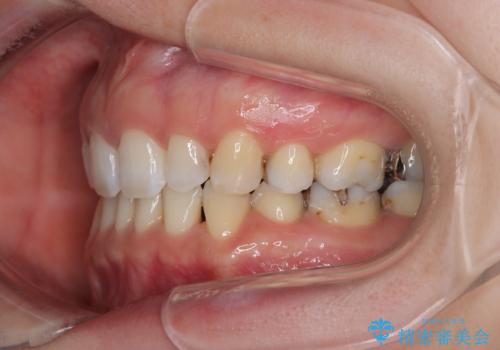

- 口元の突出感と口の閉じにくさを気にして来院された患者様です。

上下左右第一小臼歯4本を抜歯し、ワイヤー装置にて口元を引っ込めるよう矯正治療を行うこととしました。

奥歯が前方に傾斜していることで深く咬みこむ(ディープバイト)状態であったので、なかなか抜歯したスペースが閉じず、様々な方法でディープバイトを改善しながら治療を進めていくこととなりました。